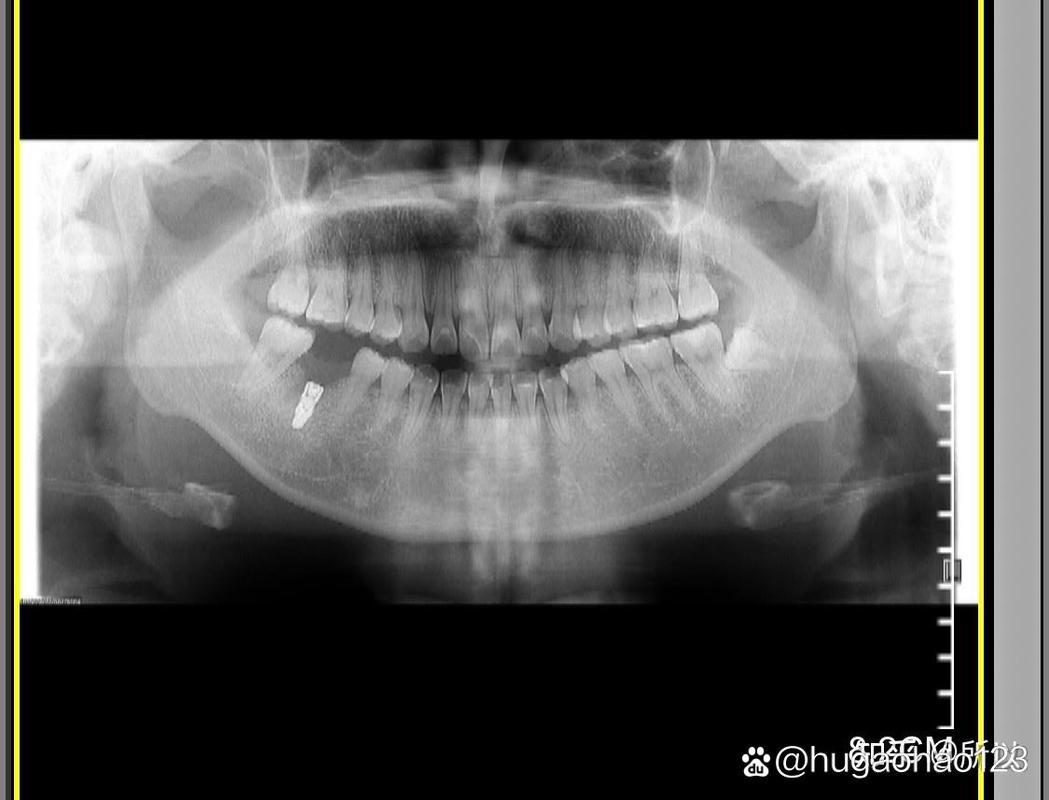

种植牙流程通常分为术前检查、方案设计、手术植入、戴冠修复及术后维护五个阶段,术前需进行口腔全景片、血常规等检查,评估骨量、全身健康状况;方案设计阶段,医生会结合患者咬合习惯、美学需求制定个性化方案;手术植入在局部麻醉下进行,一般30分钟至1小时完成;骨整合期(3-6个月)后,安装基台和牙冠,最终完成修复,整个过程需患者与医生密切配合,术后定期复查以确保种植体长期稳定。